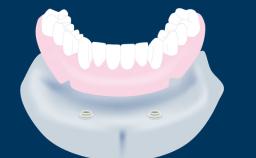

Fixed and removable prosthodontic implant therapy for restoration of the edentulous maxilla is both complex and challenging. Careful assessment and planning is needed in each individual case to explore whether a fixed or a removable solution will be the more suitable to satisfy the patient’s preference for optimal esthetics, phonetics, comfort and function. This Learning Pathway explores the prosthodontically driven treatment planning based on structured assessment, considered diagnosis and practical application in clinical case examples.

• identify decisive factors based on structured assessment and treatment planning